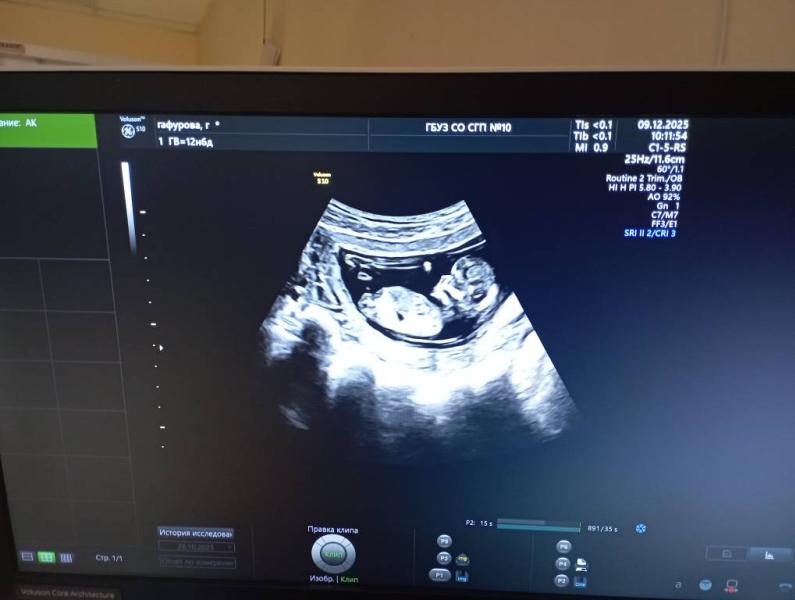

Всем приветик, сегодня была на первом скрининге,фото не дали конечно,но с экрана сфоткать разрешили,и хотела узнать мнение со стороны,кого вы видите ,я думаю что мальчик(узистка сказала что ей тоже так показалось) #первыйпост

На этом сроке определяют по углу полового бугорка. По данному фото никак не предположить)) опытный узист может в моменте конечно предположить, и то это будет не точное попадание

Ну с этого ракурса не смотрят, мальчик или девочка, тут 50/50.